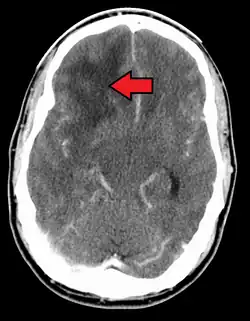

| A coronal view (from the back of the head) of a contrast-enhanced MRI revealing a glioblastoma in a 15-year-old boy | |

When viewed with MRI, glioblastomas often appear as ring-enhancing lesions. The appearance is not specific, however, as other lesions such as abscess, metastasis, tumefactive multiple sclerosis, and other entities may have a similar appearance.[61] Definitive diagnosis of a suspected GBM on CT or MRI requires a stereotactic biopsy or a craniotomy with tumor resection and pathologic confirmation. Because the tumor grade is based upon the most malignant portion of the tumor, biopsy or subtotal tumor resection can result in undergrading of the lesion. Imaging of tumor blood flow using perfusion MRI and measuring tumor metabolite concentration with MR spectroscopy may add diagnostic value to standard MRI in select cases by showing increased relative cerebral blood volume and increased choline peak, respectively, but pathology remains the gold standard for diagnosis and molecular characterization.